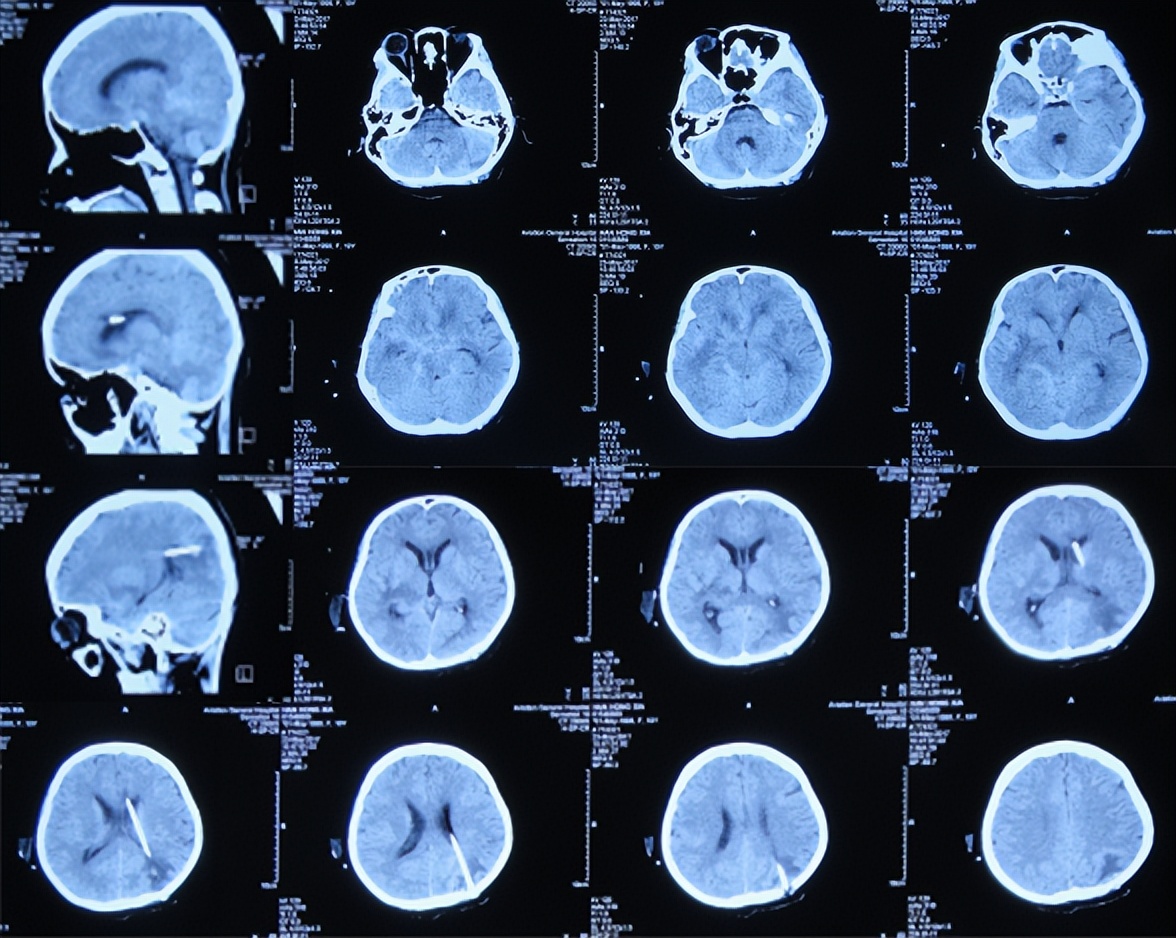

入院治疗78天即2017年8月4日,查脑增强MRI示颅内多发结核脓肿,数量仍多( 图-19 ),继续给予相关治疗。

图-19: 2017年8月4日增强脑核磁

继续治疗2月余,颅内结核脓肿数量显著减少,脑脊液生化、常规未见明显禁忌后,于入院治疗151天即2017年10月16日,进行了脑室腹腔分流术( 图-20 )。

图-20: 2017年10月16日脑CT

2017年12月20日(入院治疗7个月)完全康复出院,出院时:神清语明,肢体活动正常,走路正常,出院时脑增强MRI颅内结核脓肿有显著减少( 图-21 )。

图-21: 2017年12月20日出院时